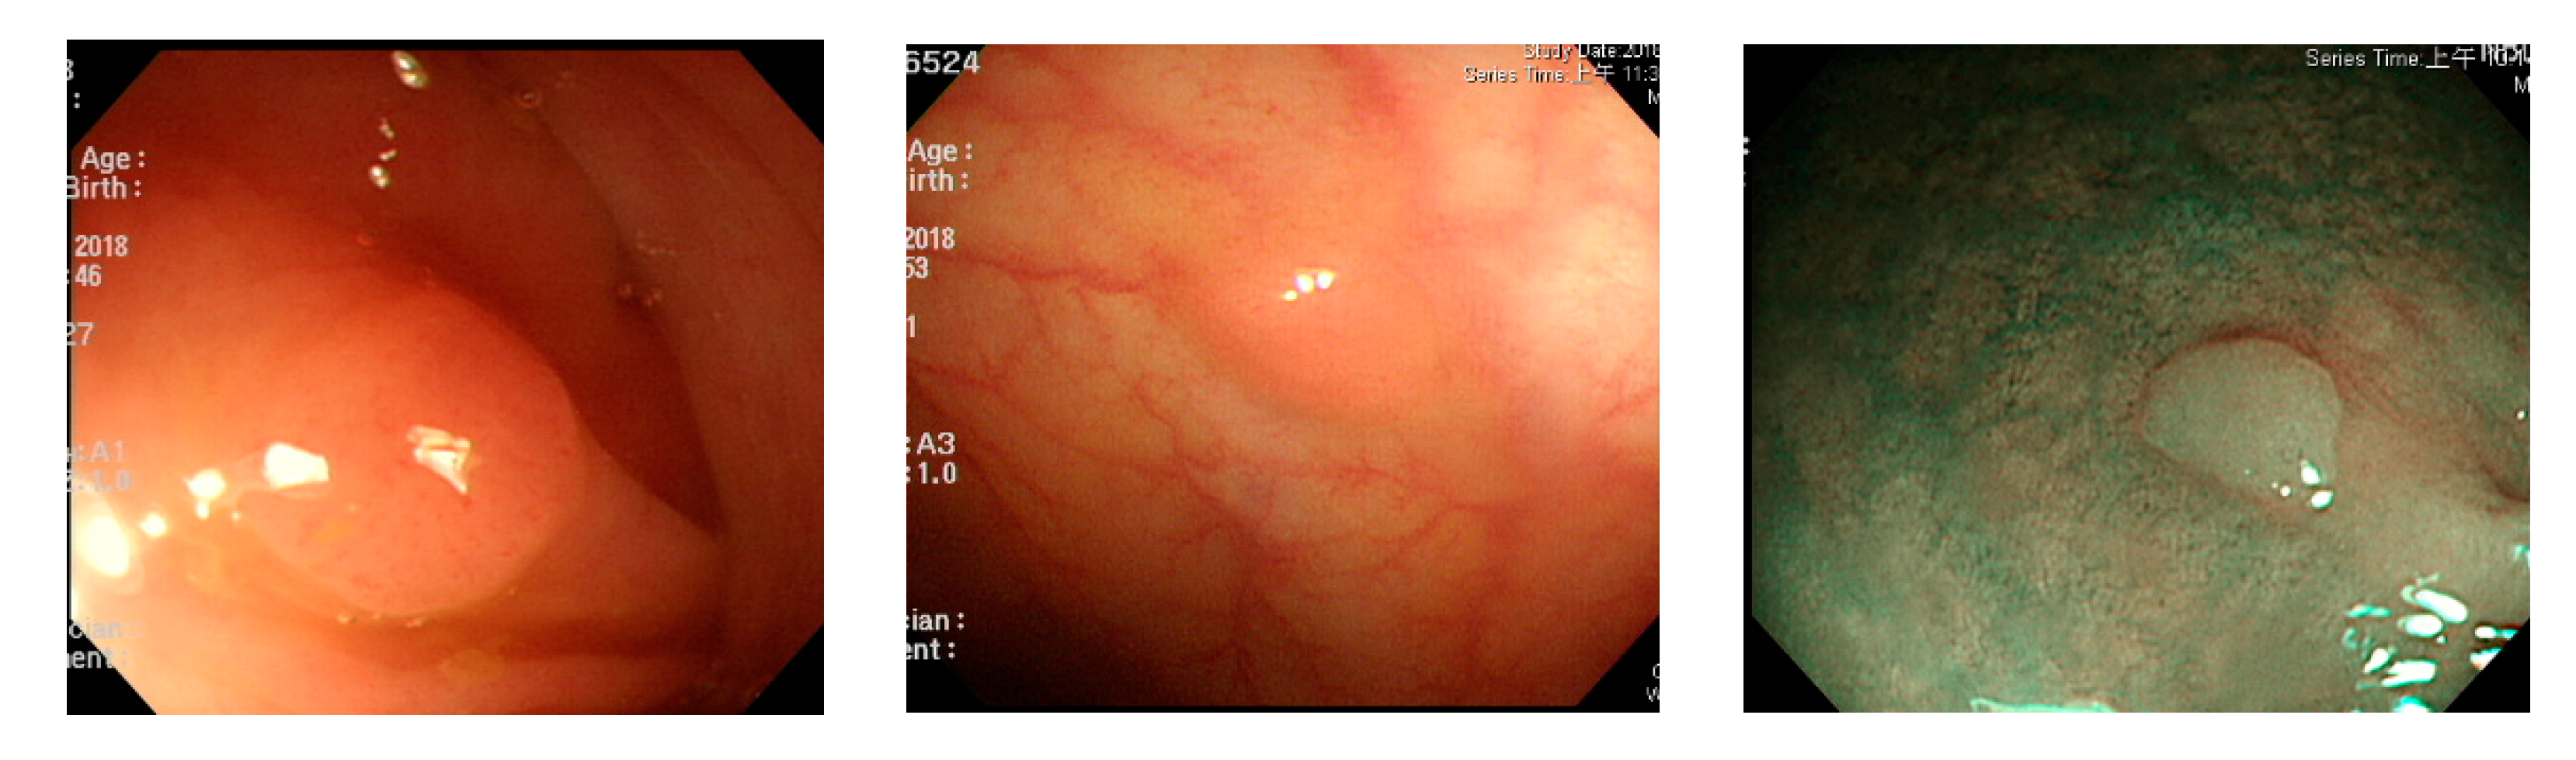

Figure 2.

Excessive intestinal wall textures with small polyps.

Figure 3.

Small texture of polyp and intestinal wall.

Currently, many medical images are processed into grayscale images, such as ultrasound, computed tomography (CT), and magnetic resonance (MR) images. Tan et al. [44] applied a gray-level cooccurrence matrix and CNN to CT images for polyp diagnosis. Zhang et al. [45] compress the three-channel color images of chest CT to grayscale images. A five-layer deep CNN with stochastic pooling is used to diagnose chest-based COVID-19. Xie et al. [46] mentioned that in deep learning, colors are not the key features influencing accurate image classification. They also discovered that in X-ray image classification, the speed and accuracy of processing grayscale images were considerably higher than those of processing RGB images. The grayscale method used was ITU-R Recommendation BT.601 [47]. Moreover, misjudgments were easily made in the presence of excessive intestinal wall textures, when polyps were too small (Figure 2), and when polyp textures were similar (Figure 3) to intestinal wall textures.